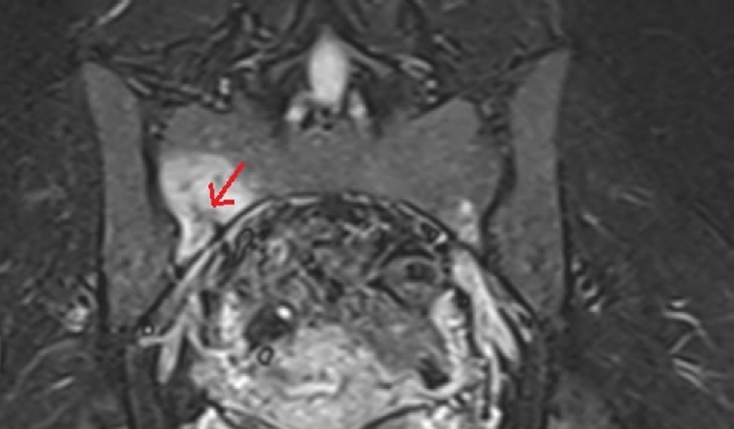

A 30-year-old female healthcare worker presented with localized deep gluteal pain. A hip MRI was performed; however, the initial report did not address the sacrum. Following clinical–radiologic correlation and targeted re-evaluation, the MRI demonstrated findings consistent with a unilateral sacral stress fracture pattern involving the sacral ala. MRI assessment included fluid-sensitive sequences covering the sacral alae, specifically coronal short tau inversion recovery (STIR) and fat-suppressed T2-weighted images with a field of view encompassing the sacrum (

Fig. 1). This appearance may be misinterpreted as nonspecific periarticular marrow edema if the sacrum is not deliberately incorporated into the imaging search pattern [

Fig. 1.Hip magnetic resonance imaging (patient A). Imaging demonstrates a unilateral sacral ala stress fracture pattern with surrounding marrow edema, best appreciated on fluid-sensitive sequences. The arrow indicates bone marrow edema in the sacral ala with a visible fracture line.